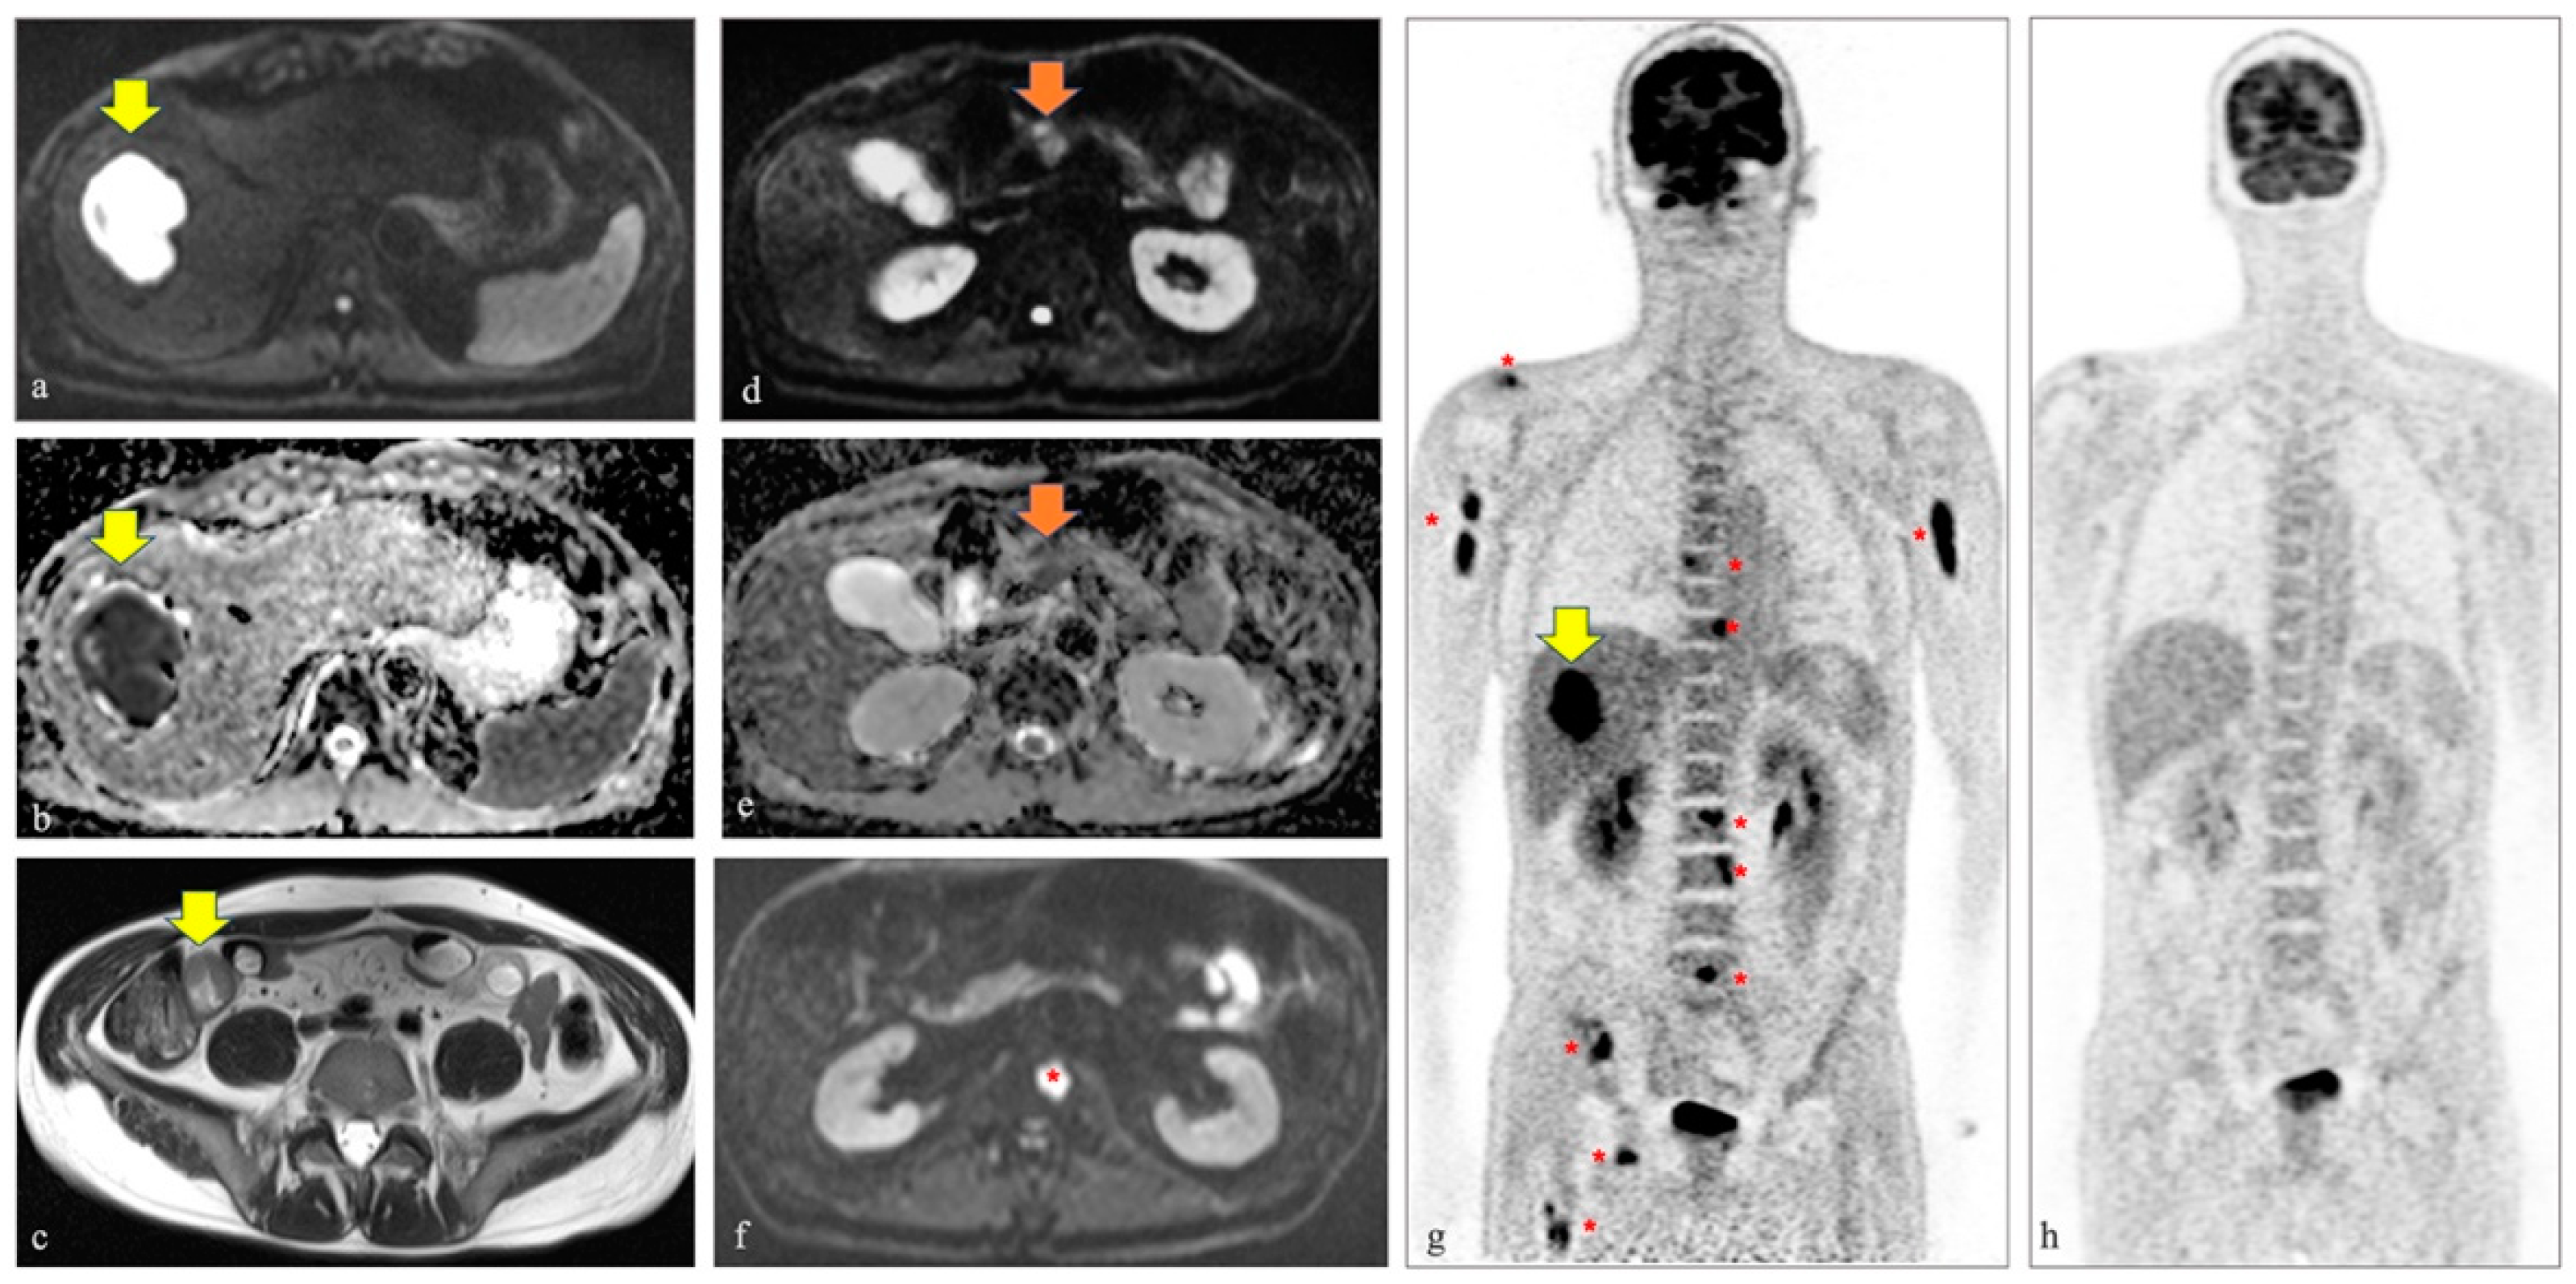

Although PET/magnetic resonance (MR), including diffusion weighted imaging (DWI), demonstrated to be very accurate for lymphomas in general, its current application for Burkitt lymphoma is scarce [2,6,7,8]. In our case, PET/MR demonstrated to be very useful since functional and metabolic information, simultaneously collected, revealed multiple lesions (i.e., hepatic, pancreatic, and skeletal) that were not visible otherwise, on CT or basic MR sequences (Figure 1). Moreover, it should be highlighted that our patient represents a rare case of full response to treatment since, typically, the survival rate in adults is usually low (i.e., 33% of 5-year survival rate in patients older than 60) (Figure 1) [9,10].

Figure 1.

A 46-year-old male was admitted to the Emergency Room of our tertiary center because of diplopia, left orbital pain, and a two-week headache. At clinical assessment, ptosis and left III and VI cranial nerve palsy were diagnosed. The laboratory tests were unremarkable, except for high levels of lactate dehydrogenase. An MR scan of the head and neck demonstrated thrombosis of the left cavernous sinus. Then, the patient underwent a whole-body contrast enhanced CT and a thickening of the small intestine and a large hepatic lesion, although not typical for any specific disease, were identified. Given the not univocal findings at CT and aiming to better characterize the hepatic and intestinal lesions, also in terms of metabolic activity, the referring clinicians decided to move further with the diagnostic workflow. A few days later, a 18F-FDG-PET/MR including DWI was performed and confirmed the above-mentioned lesions. In particular, on the axial DWI image (i.e., b value 800) and corresponding ADC map in (a,b) the restricted diffusion of the liver lesion is well seen (yellow arrows), while in (g) the high metabolic activity at PET of the same hepatic lesion is detected (yellow arrow on the coronal map of the PET component). Moreover, on the axial T2 half-Fourier single-shot turbo spin-echo image, the thickening of the small bowel was easily identified (yellow arrow in (c)). Only DWI images and PET maps demonstrated additional hepatic nodules, a pancreatic mass (orange arrows in (d,e) demonstrating the pancreatic lesion characterized by restricted diffusion on the axial DWI image at b 800 and the corresponding ADC map, respectively), and bone metastases (red asterisk in (f) on the axial DWI image demonstrating one of the bone metastases affecting the second lumbar vertebra and multiple red asterisks on the PET map in (g), demonstrating the high metabolic activity of the numerous skeletal lesions). Hepatic and bone marrow biopsies revealed the diagnosis of Burkitt lymphoma. The patient immediately started chemotherapy and after four cycles of rituximab, cyclophosphamide, doxorubicin, vincristine, methotrexate/ifosfamide, etoposide, and high dose cytarabine (R-CODOX-M/IVAC), a complete metabolic response occurred, as is well seen on the coronal PET map obtained after treatment (i.e., four months after the first PET/MR scan) in (h).